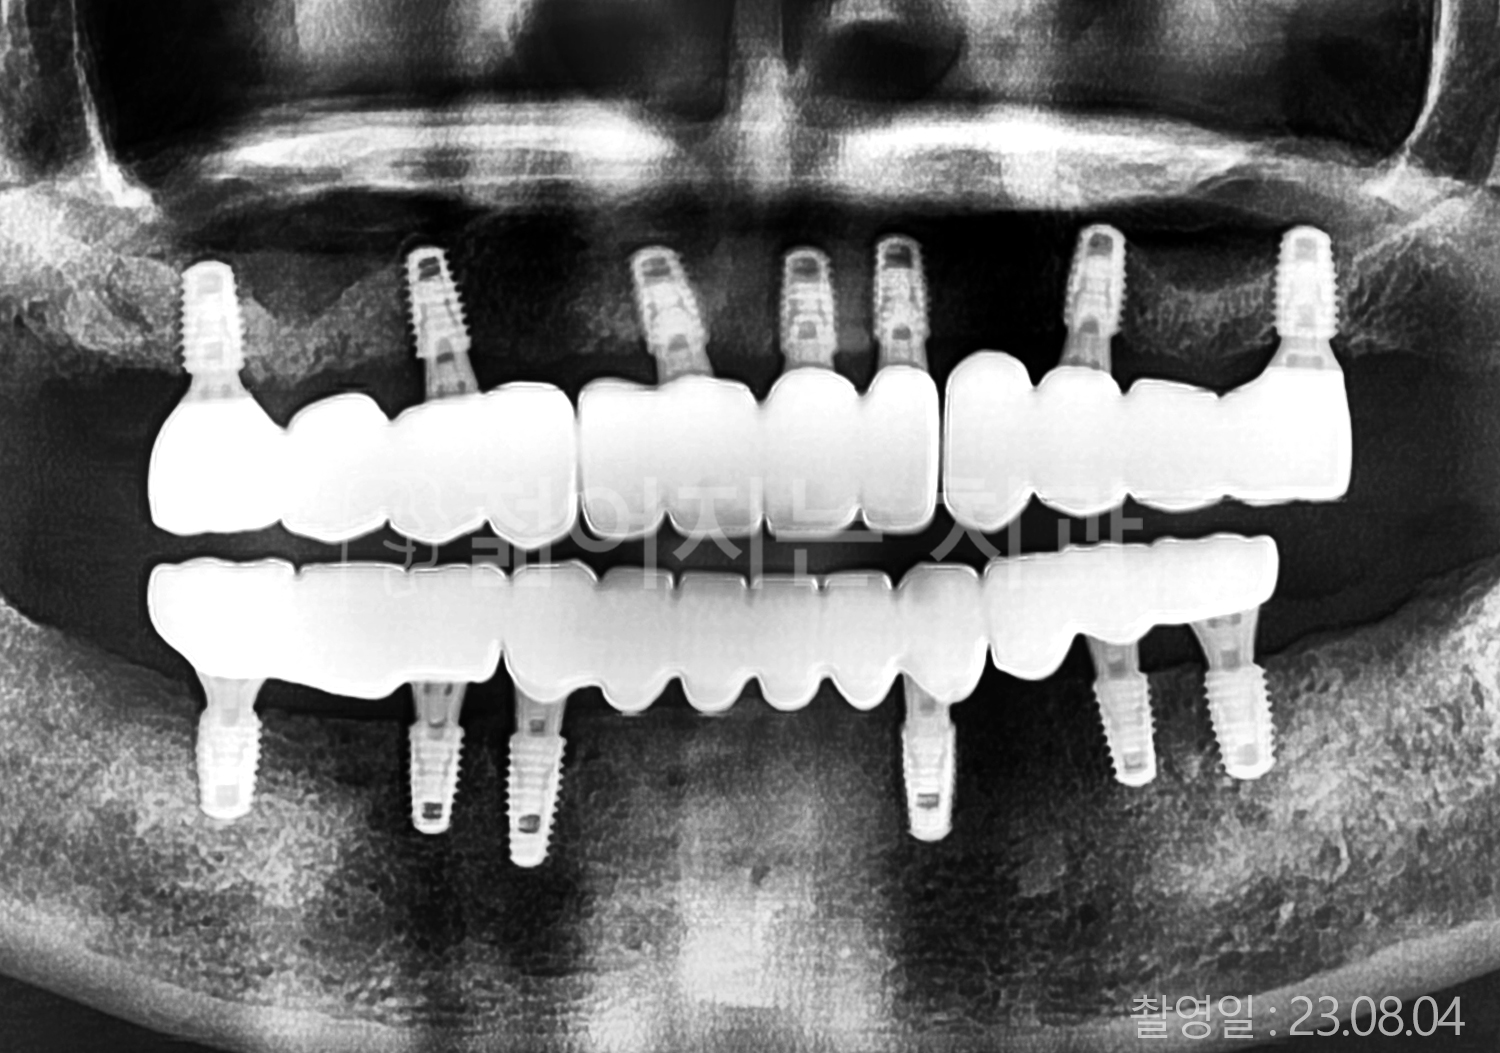

• 50대 고혈압, 당뇨, 고지혈증 전체치아 10개 이상 임플란트

• 60대 골다골증, 간경화 전체치아 10개 이상 임플란트

• 60대 고혈압, 고지혈증 전체치아 10개 이상 임플란트

• 50대 고혈압, 당뇨 전체치아 10개 이상 임플란트

• 60대 고혈압 전체치아 10개 이상 임플란트

• 60대 전체치아 10개 이상 임플란트

• 60대 고지혈증 전체치아 10개 이상 임플란트

• 40대 전체치아 10개 이상 임플란트

• 70대 전체치아 10개 이상 임플란트